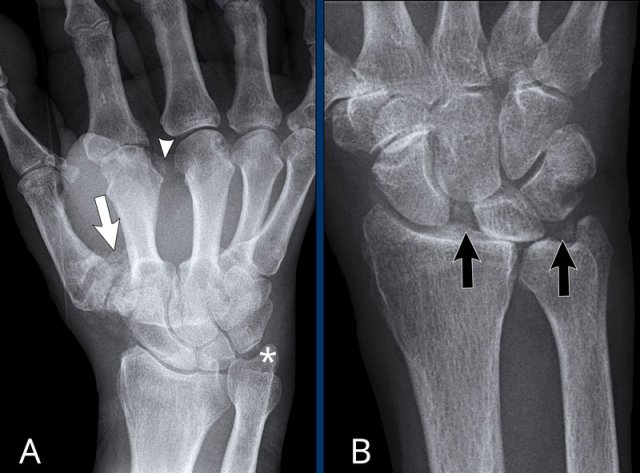

Two patients with typical CPPD.

A. There is cartilage loss in many joints and chondrocalcinosis in:

• CMC1 (white arrow)

• MCP joints (arrowhead)

• TFCC (asterix)

B. This patient had an acute joint inflammation. Chondrocalcinosis in the radiocarpal joint and the TFCC (black arrows) is seen, almost pathognomonical for CPPD. There is scapholunate dissociation, which can be seen in CPPD, but also in rheumatoid arthritis or posttraumatic.

This sudden attack is called pseudogout, because it can simulate the inflammation and intense pain of a gout attack.